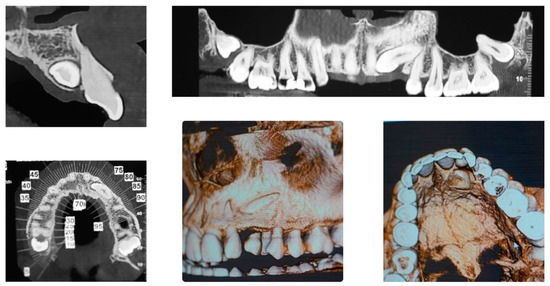

An adult female patient, 43 years old, with Class I occlusion on both sides and with a slight deep bite, light crowding, a persistent deciduous canine no. 63, and a horizontally impacted canine with the crown tip close to the lateral incisors and the tip of the root protruding beyond the buccal bone in the 2.3 area is presented in Figure 9 and Figure 10.

Figure 9.

Class I occlusion on both sides with a slight deep bite, light crowding, a persistent deciduous canine no. 63, and a horizontally impacted canine with the tip of the crown close to the lateral incisors and the tip of the root protruding beyond the buccal bone in the 2.3 area.

Figure 10.

CBCT pictures of the patient. Since the patient was subjected to periodic radiographic control as she was a cancer survivor, the decision was to do a CBCT to receive all the informations useful for the deimpaction treatment and avoid conventional orthodontic X-rays like panoramic and lateral X-rays.